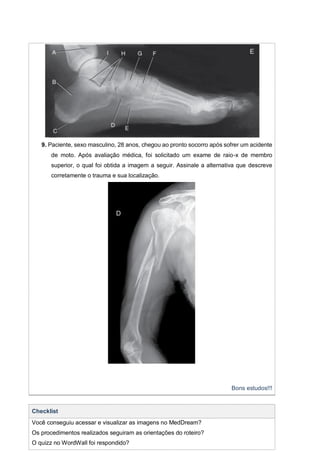

9. Paciente, sexo masculino, 28 anos, chegou ao pronto socorro após sofrer um acidente

de moto. Após avaliação médica, foi solicitado um exame de raio-x de membro

superior, o qual foi obtida a imagem a seguir. Assinale a alternativa que descreve

corretamente o trauma e sua localização.